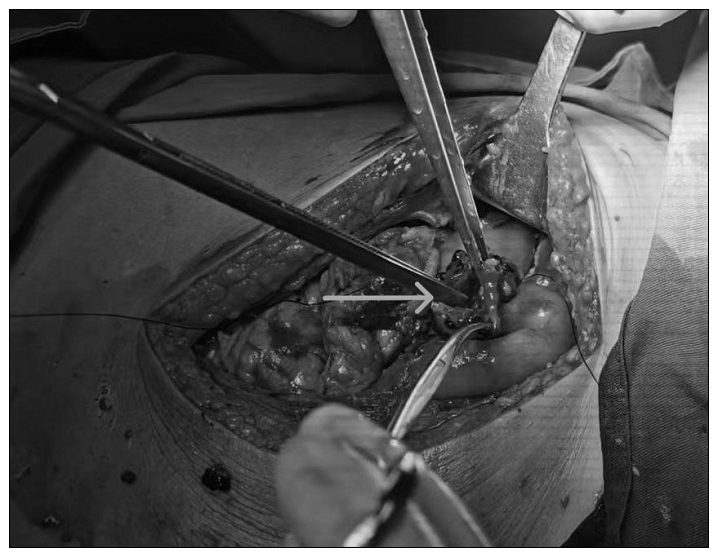

多学科团队没有畏惧,更没有放弃,按照之前制定的详细的严重肝破裂救治流程果断进行抢救。各单位分工协作,联系血库备血,手术室准备好自体血回输,麻醉团队就位,介入科进行肝动脉栓塞,急诊外科紧急开腹。探查系肝脏右叶大面积裂伤,中央型肝破裂,实质破裂累计约60%肝叶,深度达8cm,右肝静脉撕裂,下腔静脉撕裂,腹腔活动性出血。依据美国创伤外科协会(American Association for the Surgery of Trauma)的肝外伤评估标准(2018年),此例患者达到最高等级Ⅴ级!在血库的充足供血、麻醉科的有效麻醉管理下,手术团队成功完成了右肝的大部切除和下腔静脉修补,实现了一期止血。